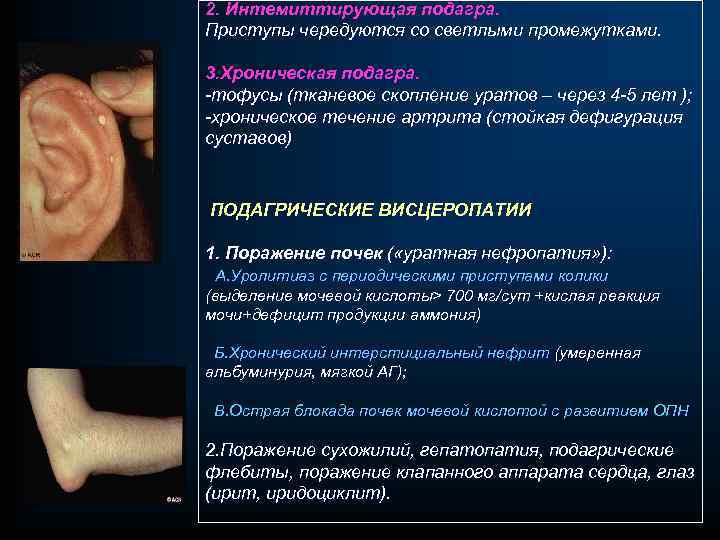

2. Интемиттирующая подагра. Приступы чередуются со светлыми промежутками. 3. Хроническая подагра. -тофусы (тканевое скопление уратов – через 4 -5 лет ); -хроническое течение артрита (стойкая дефигурация суставов) ПОДАГРИЧЕСКИЕ ВИСЦЕРОПАТИИ 1. Поражение почек ( «уратная нефропатия» ): А. Уролитиаз с периодическими приступами колики (выделение мочевой кислоты> 700 мг/сут +кислая реакция мочи+дефицит продукции аммония) Б. Хронический интерстициальный нефрит (умеренная альбуминурия, мягкой АГ); В. Острая блокада почек мочевой кислотой с развитием ОПН 2. Поражение сухожилий, гепатопатия, подагрические флебиты, поражение клапанного аппарата сердца, глаз (ирит, иридоциклит).

2. Интемиттирующая подагра. Приступы чередуются со светлыми промежутками. 3. Хроническая подагра. -тофусы (тканевое скопление уратов – через 4 -5 лет ); -хроническое течение артрита (стойкая дефигурация суставов) ПОДАГРИЧЕСКИЕ ВИСЦЕРОПАТИИ 1. Поражение почек ( «уратная нефропатия» ): А. Уролитиаз с периодическими приступами колики (выделение мочевой кислоты> 700 мг/сут +кислая реакция мочи+дефицит продукции аммония) Б. Хронический интерстициальный нефрит (умеренная альбуминурия, мягкой АГ); В. Острая блокада почек мочевой кислотой с развитием ОПН 2. Поражение сухожилий, гепатопатия, подагрические флебиты, поражение клапанного аппарата сердца, глаз (ирит, иридоциклит).